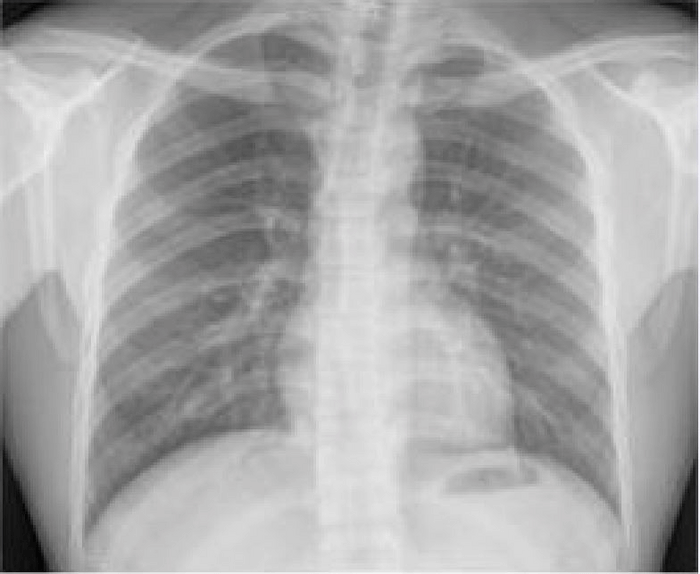

CHICAGO — A patient’s risk of a heart attack or stroke in the next 10 years can be predicted from just one chest X-ray by a new computer system.

Researchers with the Radiological Society of North America say it combines AI (artificial intelligence) with a standard X-ray to find patterns associated with hardening of the arteries. The technique offers hope that doctors will be able to prescribe vulnerable individuals cholesterol-reducing drugs before it’s too late.

The U.S. team trained the model, known as CXR-CVD risk, to predict death from cardiovascular disease using 147,497 chest X-rays from 40,643 participants in a cancer screening trial.

In tests, the system accurately predicted heart attacks and strokes in a group who had routine chest X-rays at Mass General Brigham. About 10 percent of the 11,430 outpatients suffered a major cardiac event over the average follow-up of just over a decade. The system also identified those who were eligible for potentially life-saving statin therapy.

“The beauty of this approach is you only need an X-ray, which is acquired millions of times a day across the world,” the study author explains. “Based on a single existing chest X-ray image, our deep learning model predicts future major adverse cardiovascular events with similar performance and incremental value to the established clinical standard.”